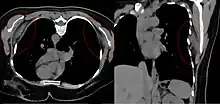

| Bilateral elastofibroma dorsi in native computed tomography: left image axial in prone position (for biopsy), right image oblique coronal view. |

By computed tomography, there is a poorly circumscribed, heterogeneous soft tissue mass, with a signal intensity similar to skeletal muscle. The fact that the lesion may be bilateral, helps eliminate a sarcoma from further consideration.[5] At US, elastofibromas are depicted deep to the musculature as a multilayered pattern of hypoechoic linear areas of fat deposition intermixed with echogenic fibroelastic tissue.[6] The mass often protrudes from the subscapular region upon shoulder abduction, allowing better delineation of the finding.[7]